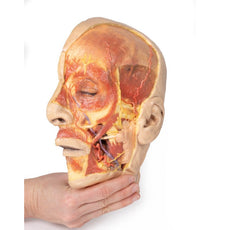

On the opposing side of the model, a superficial and deep dissection has

opened a large window into the anatomy of the lateral scalp and infratemporal

fossa. Across the scalp there is a well preserved posterior auricular nerve

and superficial temporal artery highlighted on the superficial surface of the

temporalis muscle. Anteriorly, the temporalis has been dissected to expose

the deep temporal arteries arising from across the maxillary artery.

The deep level of dissection has exposed parts of the infratemporal fossa

(through partial removal of the mandibular ramus and corpus) and dissection

of retromandibular tissues. At the inferior margin of the dissection window,

the cut edge of the retromandibular vein lies adjacent to the submandibular

gland and the ascending path of the facial artery as it cross towards to angle

of the mouth. Just superior to the cut retromandibular vein is the posterior

belly of the digastric muscle, overlying a small exposure of the deeper

internal jugular vein.